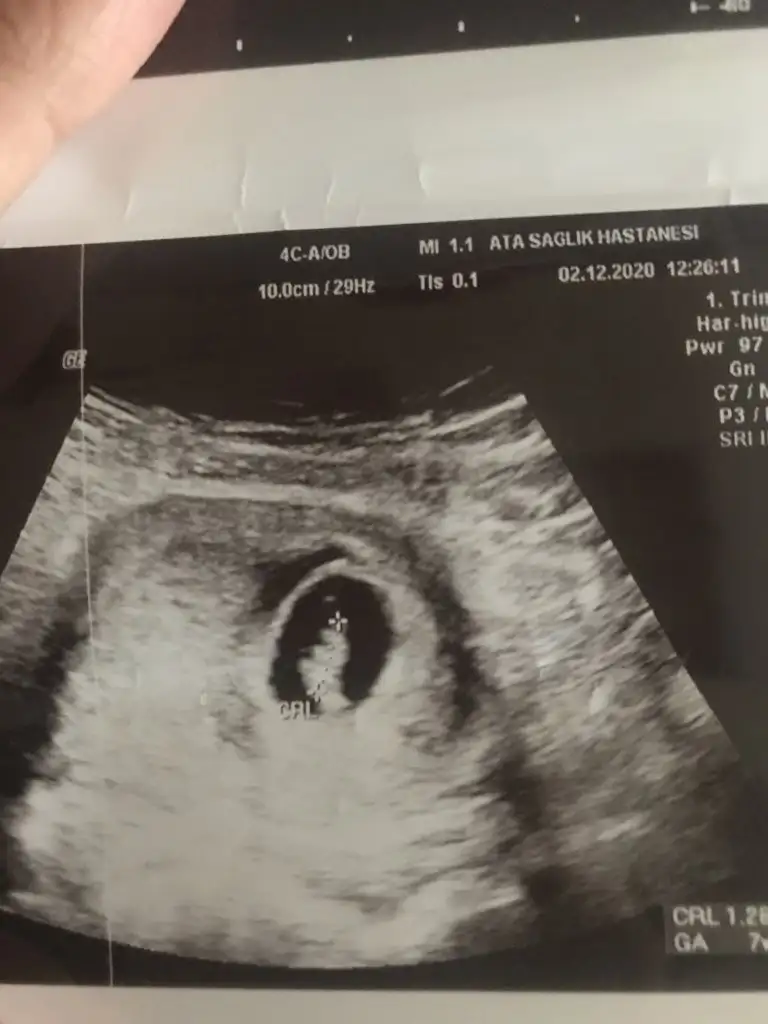

Eki Görüntüle 2727392

çok teşekkür ederim anlamadığım neredinden anlıyorsunuz ben saatlerce baksam ne olduğunu anlayamam nasıl anlıyorsunuz bu kadar net kız veya erkek diyebiliyorsunuz aslında buda bir marifet helal valla